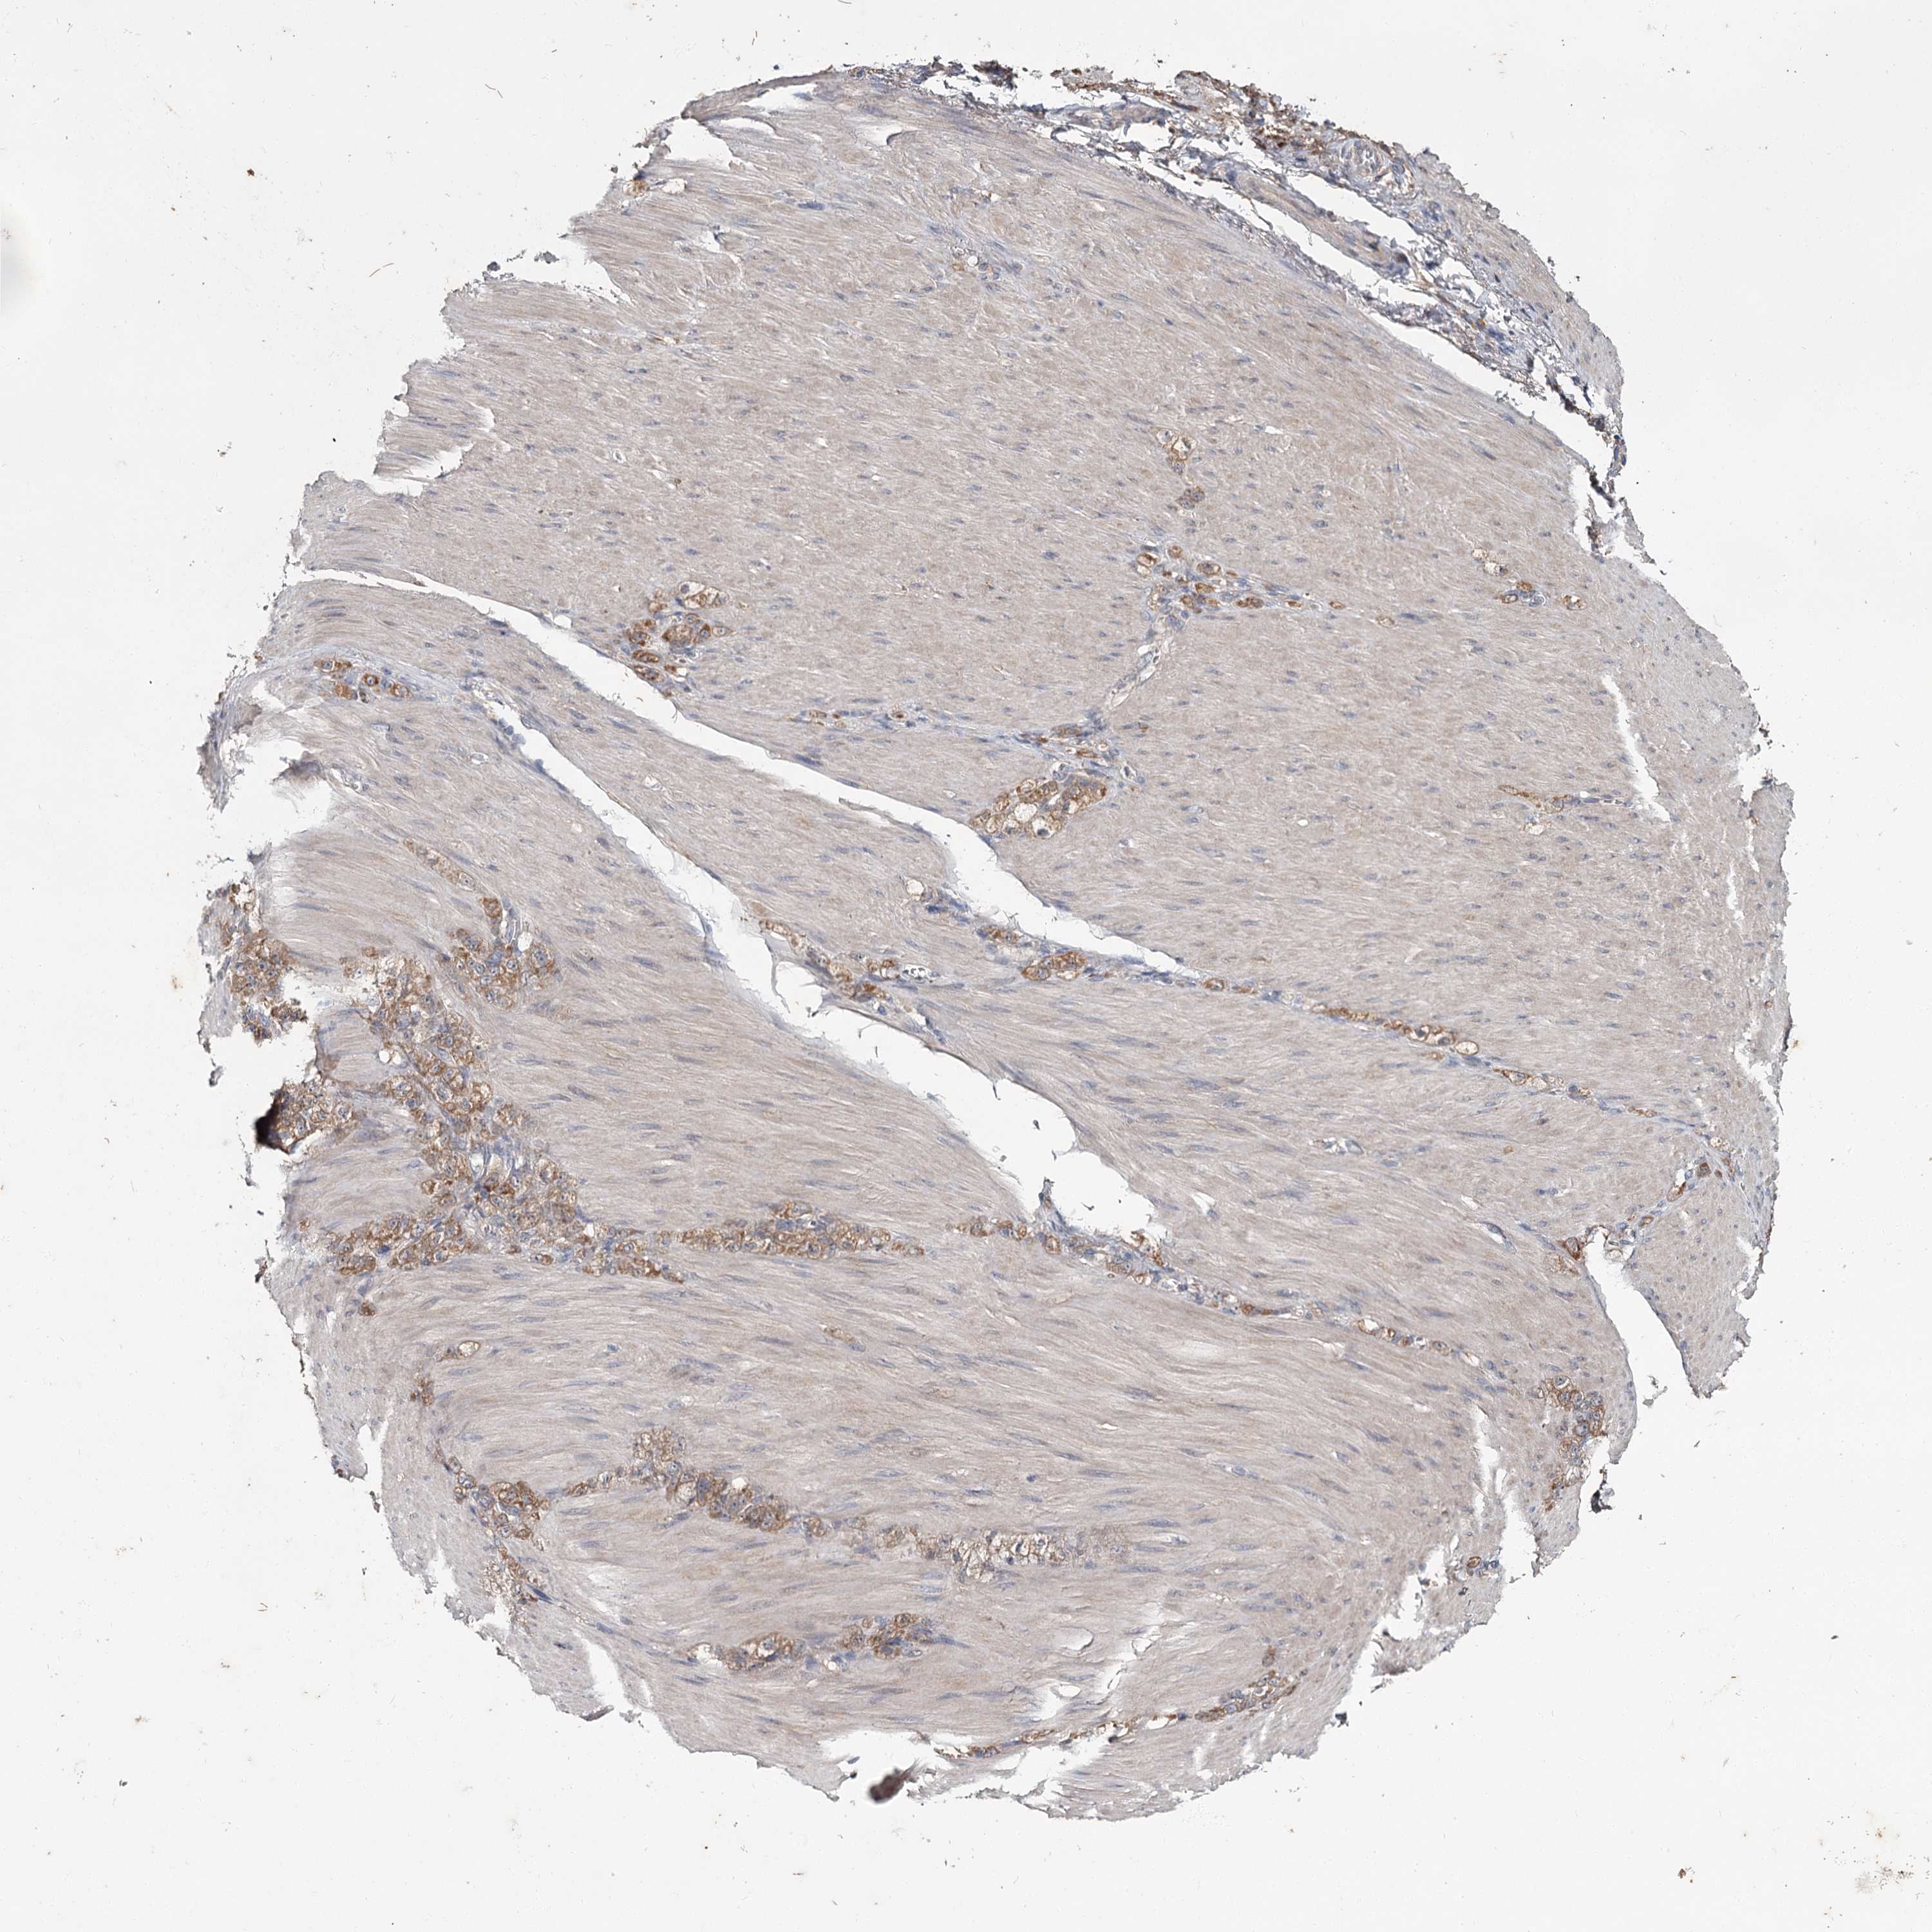

STOMACH CANCER - Protein expressioni

A mouse-over function shows sample information and annotation data. Click on an image to view it in a full screen mode. Samples can be filtered based on level of antibody staining by selecting one or several of the following categories: high, medium, low and not detected. The assay and annotation is described here.

Note that samples used for immunohistochemistry by the Human Protein Atlas do not correspond to samples in the TCGA dataset.

Antibody stainingi

Antibody staining in the annotated cell types in the current human tissue is reported as not detected, low, medium, or high, based on conventional immunohistochemistry profiling in selected tissues. This score is based on the combination of the staining intensity and fraction of stained cells.

Each image is clickable and will lead to virtual microscopy that enables deeper exploration of all samples and also displays staining intensity scores, fraction scores and subcellular localization as well as patient and tissue information for each sample.

Antibody CAB033437

Staining

High

Medium

Low

Not detected

Intensity

Strong

Moderate

Weak

Negative

Quantity

>75%

75%-25%

<25%

None

Location

Nuclear

Cytoplasmic/membranous

Cytoplasmic/membranous,nuclear

Adenocarcinoma, NOS